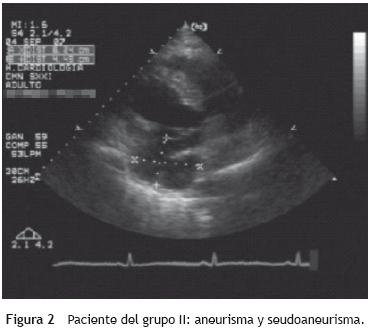

A los 30 días después del infarto se repitió el estudio ecocardiográfico; 20 (55,5%) pacientes ya habían sido cateterizados en un rango de 10 ±3 días del evento. En 11 (55%) pacientes se realizó una angioplastia transluminal percutánea (ACTP) de la arteria involucrada; en 10 (90,9%) pacientes fue exitosa y hubo 1 (9,09%) ACTP fallida. En este paciente se encontraron, en el momento del estudio ecocardiográfico, un aneurisma y un seudoaneurisma posterolateral (grupo II) (fig. 2). No se observaron cambios significativos en la relación E/A y el tipo de infarto; sin embargo, se observó un incremento en el TD: 170 ±55 frente a 207 ± 40 ms (p = 0,01). El VDF se incrementó a 103,69 ±16,34 y el VSF a 58,81 ± 20,36, aun en los pacientes con ACTP exitosa. La relación E/Vp disminuyó, lo que demuestra una disminución de la presión diastólica final del ventrículo izquierdo en los pacientes con ACTP exitosa (r = 0,571; p < 0,01). El índice global de contracción y el espesor de las paredes no presentaron cambios significativamente estadísticos.

En el IAM, la necrosis miocárdica es consecuencia de una obstrucción total y sostenida de la arteria coronaria causante, donde se presenta una "onda frontal" característica que se inicia pocos latidos después de la obstrucción coronaria y que va progresando en minutos, del subendocardio al sub–epicardio, por lo que es de suma importancia la reperfusión, que es la mejor medida terapéutica para disminuir el tamaño del infarto y salvar células miocárdicas isquémicas. Después de la lesión del miocardio, se inicia el proceso de remodelación ventricular7. En la remodelación temprana se presenta un primer fenómeno llamado expansión del infarto, definido como una dilatación aguda, un adelgazamiento de la pared ventricular necrótica y un "inexplicable segmento de tejido necrótico nuevo". Esto se ha atribuido a un progresivo estiramiento y separación de fibras musculares necróticas dentro de la pared miocárdica, lo que resulta en alteraciones significativas de la morfología del ventrículo izquierdo que provocan un aumento importante del VDF del ventrículo izquierdo, una ecorremodelación cardíaca post–IAM y un incremento del estrés parietal al final de la diástole y la sístole en todas las partes del ventrículo —en especial en la zona infartada— que dan como resultado una estructura miocárdica adaptativa para mantener el volumen de latido y el gasto cardíaco. La expansión severa ventricular se ha asociado con la formación de aneurismas ventriculares, así como con la rotura ventricular en el IAM. Existe otro fenómeno llamado extensión del infarto, que se define como un mayor terreno necrótico en relación con el inicial y se relaciona con el grado de permeabilidad y el tiempo de oclusión de la arteria relacionada con el infarto8,9. Hay factores que predicen la extensión del IAM y por los que, en caso de presentarse en las 48 h posteriores de haberse iniciado los síntomas, la mortalidad intrahospitalaria se eleva 4 veces más9. Los factores de riesgo para la extensión del IAM son: nueva elevación enzimática de la fracción MB de la creatincinasa (CK–MB) después de 48 h de haberse iniciado los síntomas, cuadro de angina de pecho en el segundo día de hospitalización, descenso del segmento ST en relación con el electrocardiograma inicial, infarto del miocardio previo, diabetes mellitus tipo 2, obesidad, FE < 40%, presión sistólica > 150 mmHg en las primeras 48 h, frecuencia cardíaca > 100 latidos por minuto persistente en las primeras 48 h y sexo mujer. La remodelación tardía comprende la hipertrofia ventricular como respuesta adaptativa durante la fase posterior al infarto; es una respuesta a la sobrecarga que trata de atenuar la dilatación ventricular y estabilizar la función contráctil, y provoca cambios en la geometría ventricular izquierda, que está determinada por el grado de necrosis celular. Los cambios en la geometría del ventrículo determinan una cámara ventricular con tendencia a la esfericidad (a mayor esfericidad, menor FE), mayor hipoperfusión subendocárdica, mayor disminución de la reserva coronaria, dilatación de cavidades y diferentes grados de insuficiencia mitral por dilatación del anillo mitral, lo que finalmente resulta en la etapa de insuficiencia cardíaca. La ecocardiografía es la herramienta básica en el estudio de la cardiopatía isquémica. Actualmente, la ecocardiografía Doppler permite determinar la disfunción diastólica del ventrículo izquierdo, que desempeña un papel importante en los pacientes con IAM y es el primer parámetro hemodinámico detectable, independientemente de la severidad de la disfunción sistólica10. En el presente estudio se documentó que el grado de expansión se asocia a un infarto grande. La formación de un aneurisma y un seudoaneurisma ventricular se comprobó en un infarto inicial posteroinferior y lateral, en un paciente trombolizado, sin datos de reperfusión y ACTP fallida. Esta disrupción intramural ocurrió antes de la formación de tejido cicatricial, por lo que se produjeron alteraciones significativas de la morfología del ventrículo izquierdo. La dilatación de los segmentos infartados (expansión del infarto) puede ocurrir durante la evolución del infarto de miocardio, pero la evolución de los segmentos no infartados aún es incierta. Debemos mencionar que el grado de remodelación es el éxito de la trombólisis; si luego de la trombólisis el miocardio resulta viable, entonces el tamaño del infarto puede reducirse y el grado de remodelación puede disminuirse; asimismo, los pacientes con estos factores de riesgo pueden considerarse candidatos a angiografía coronaria de forma temprana y a una posible intervención para prevenir la extensión del infarto y sus secuelas. En nuestro estudio, la expansión y la extensión del infarto se triplicaron en los pacientes que presentaron más de 2 factores de riesgo durante su hospitalización respecto a los sujetos que presentaron un solo factor de riesgo (el 15,1 frente al 5,0%).